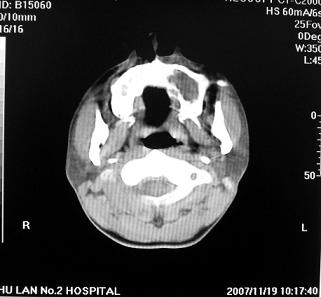

标题: CT10521:男。32岁,副鼻窦ct,请会诊。 [打印本页]

标题: CT10521:男。32岁,副鼻窦ct,请会诊。

男。32岁,鼻塞,流涕一年余。

考虑鼻腔内翻性乳头状瘤,筛窦、上颌窦炎症。建议进一步检查。

炎性病变.息肉阻塞副鼻窦口导致窦腔内潴留.

软组织密度影填满上颌蚪 筛窦及鼻腔,并导致筛骨 上颌窦内侧壁明显骨质破坏。多考虑:内翻性乳头状瘤!

双侧鼻腔内低密度软组织影,骨壁无明显破坏,鼻腔无扩大,双侧上颌窦、筛窦软组织影,窦壁增厚,结合临床考虑鼻息肉合并慢性上颌窦炎。